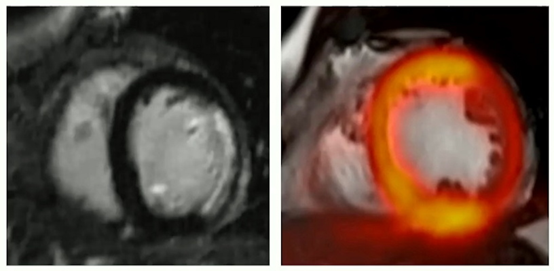

然而,在符合標準的患者中,PET/MRI可用于診斷急性心肌梗死,其中MRI提供提示心肌低代謝的晚期增強圖像,PET-FDG放射性示蹤劑攝取可進一步區分健康組織和瘢痕。

混合晚期增強MRI和PET成像有助于診斷急性心肌梗死。

她繼續說,PET/MRI也可以用于診斷急性心肌炎,事實上,在某些情況下,當感染在MRI上不明確時,它提高了診斷的可信度。這也是由于在顯示活動性炎癥的圖像中增加了PET放射性示蹤劑攝取。